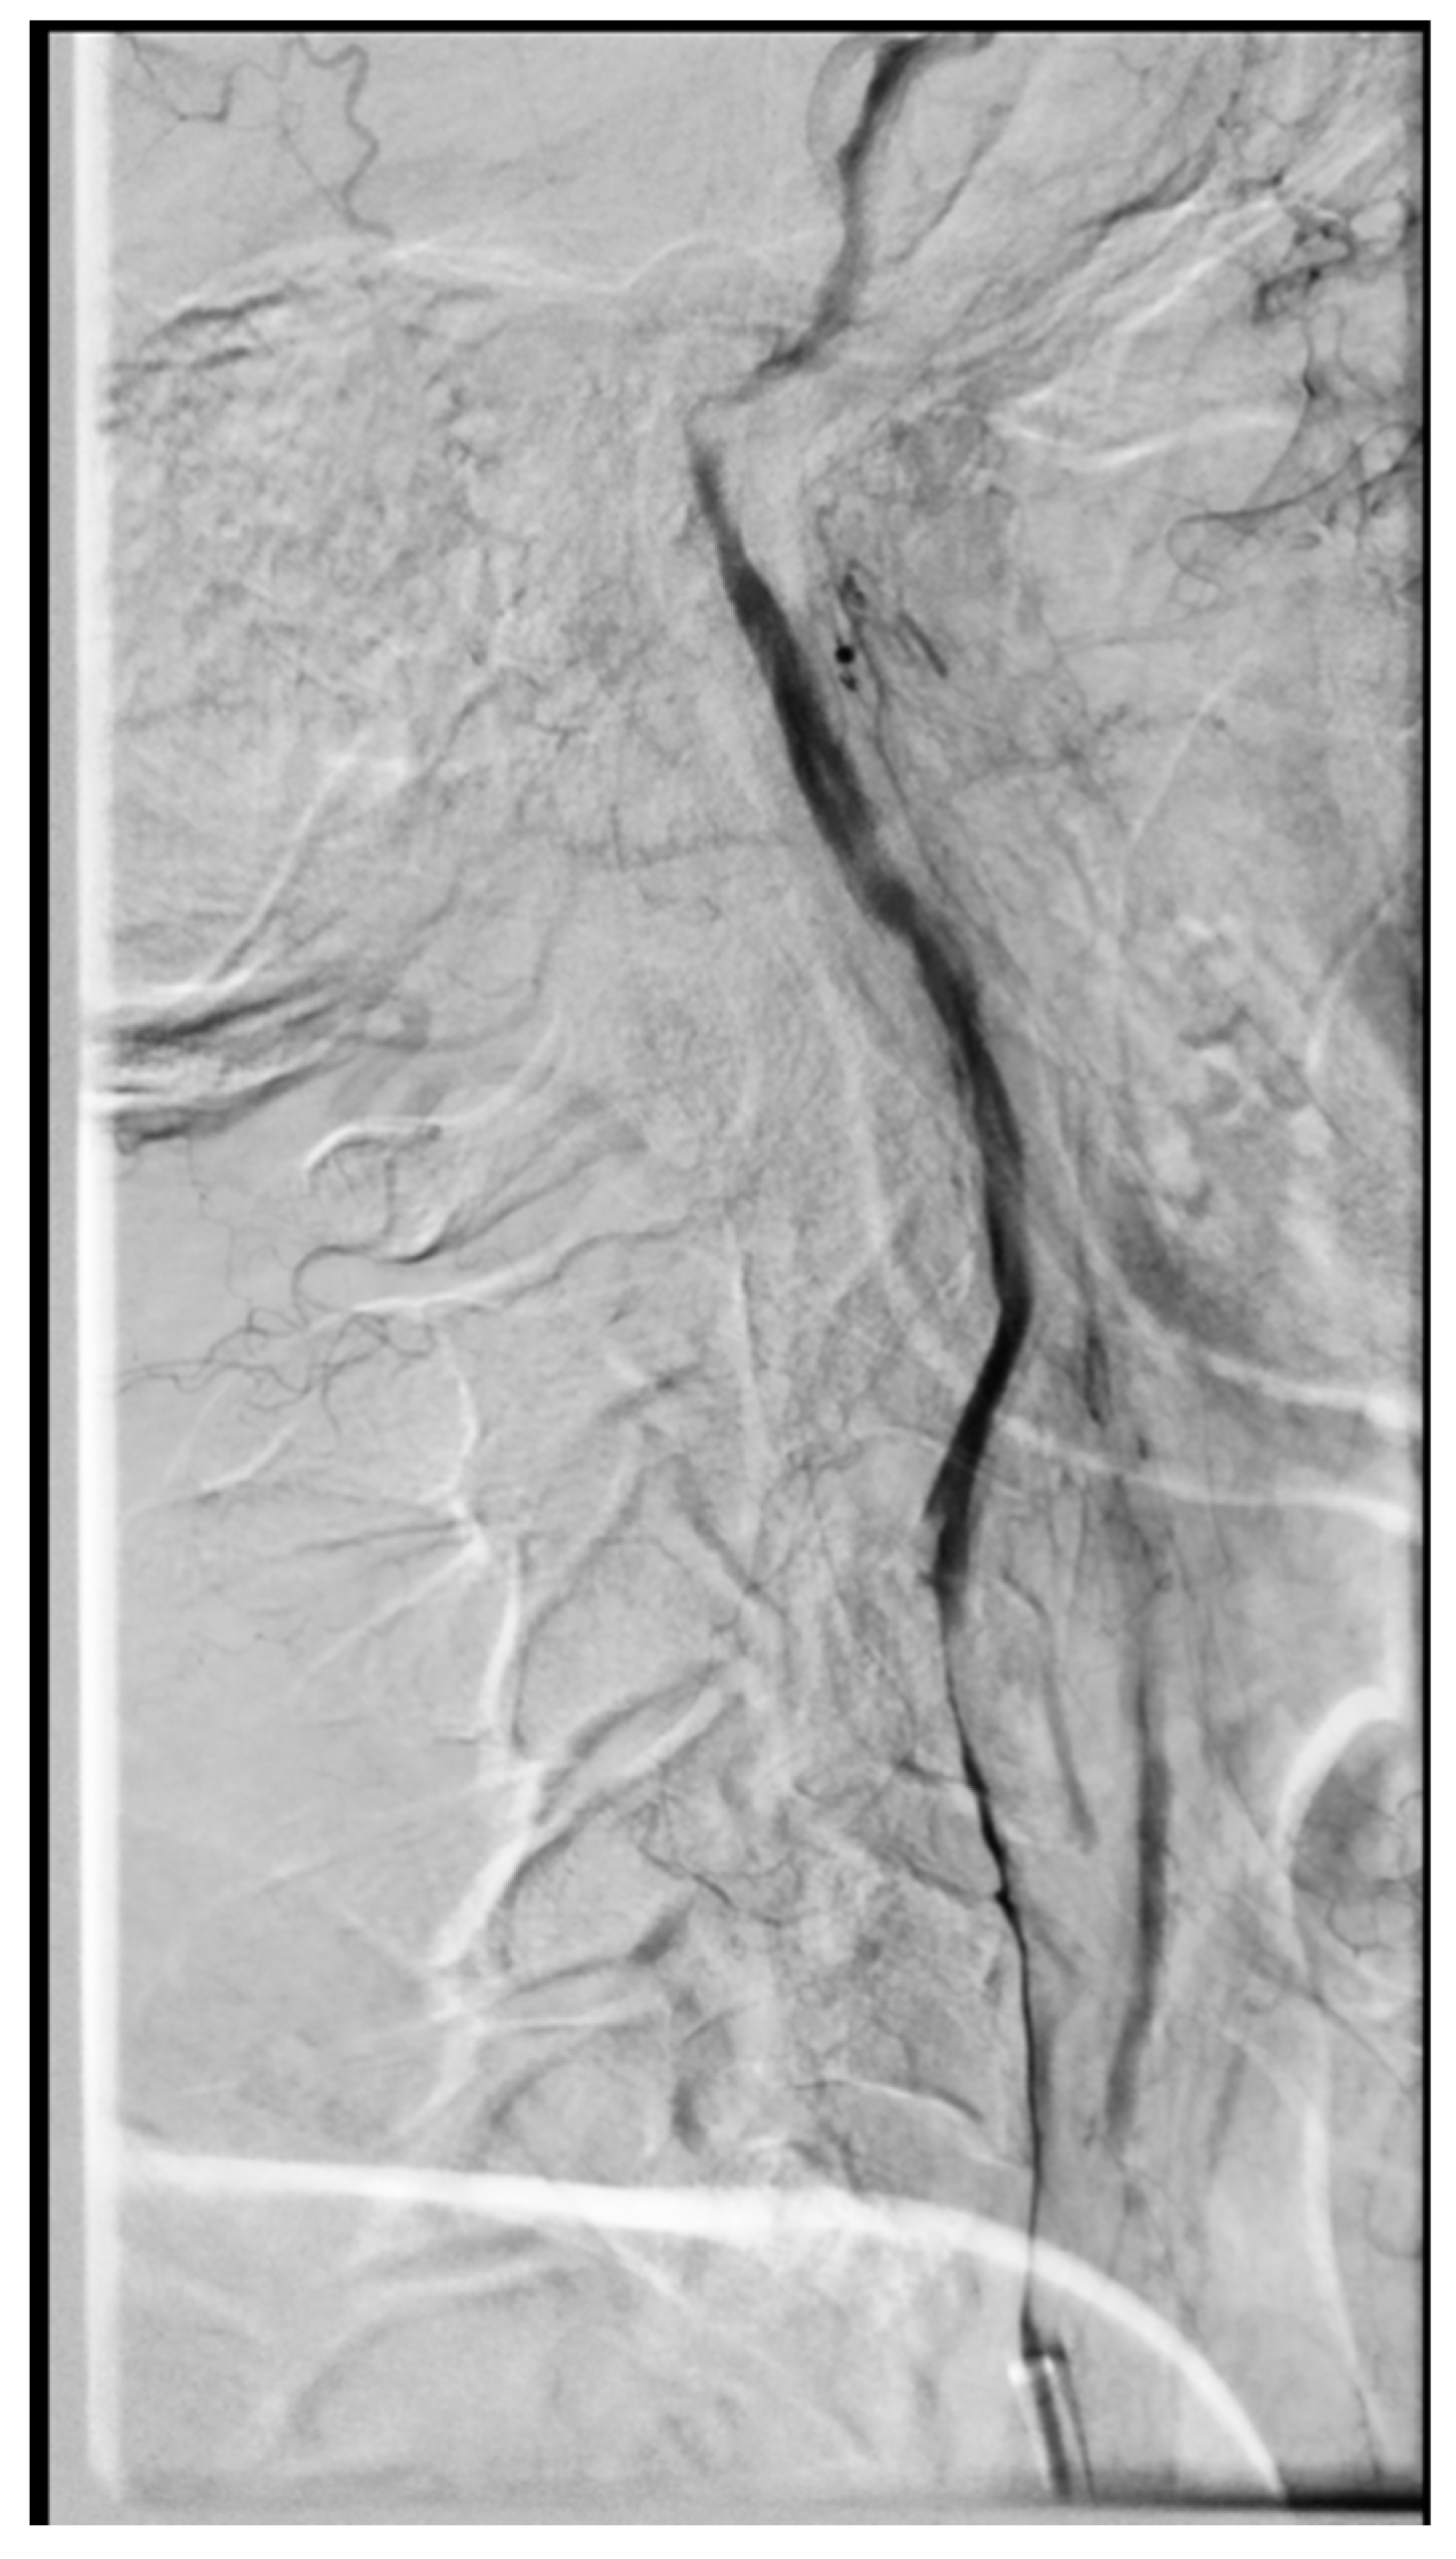

2. Case Presentation